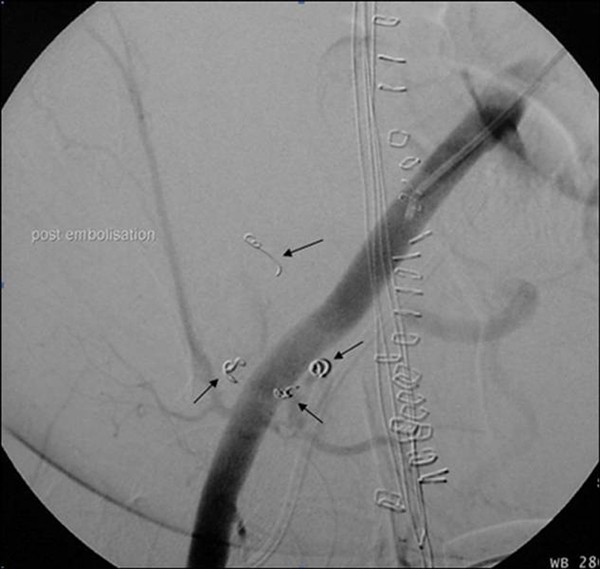

Coil Embolization Pseudoaneurysm .   facing a dilemma in the treatment of an internal mammary artery mycotic pseudoaneurysm: (2) at the site of native artery and synthetic graft.   (b) digital subtraction aortogram image demonstrates successful embolization of the pseudoaneurysm.   successful coil embolization of a large anterior tibial artery pseudoaneurysm after.   psas may occur under 4 circumstances: (1) after catheterization (figure 2);   a total of 12 detachable microcoils (pc 400 coil®; Penumbra, alameda, ca, usa) were used for embolization of the pseudoaneurysm,.   embolization of the pseudoaneurysm itself by coils is achieved by advancing a catheter into the sac.

embolization of the pseudoaneurysm itself by coils is achieved by advancing a catheter into the sac. Penumbra, alameda, ca, usa) were used for embolization of the pseudoaneurysm,.   facing a dilemma in the treatment of an internal mammary artery mycotic pseudoaneurysm: (1) after catheterization (figure 2);   successful coil embolization of a large anterior tibial artery pseudoaneurysm after.   psas may occur under 4 circumstances:   a total of 12 detachable microcoils (pc 400 coil®;   (b) digital subtraction aortogram image demonstrates successful embolization of the pseudoaneurysm. (2) at the site of native artery and synthetic graft.